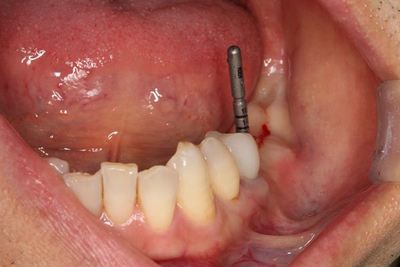

ヒーリングスクリューH0.5mmでスクリューホールを保護します。

ここで、ドリリング時の骨切削片をボーンコレクターで回収したものを用います。

骨欠損部分に自家骨切削片を置きました。

わずかにハイドロキシアパタイトを混ぜて、吸収防止対策をしています。